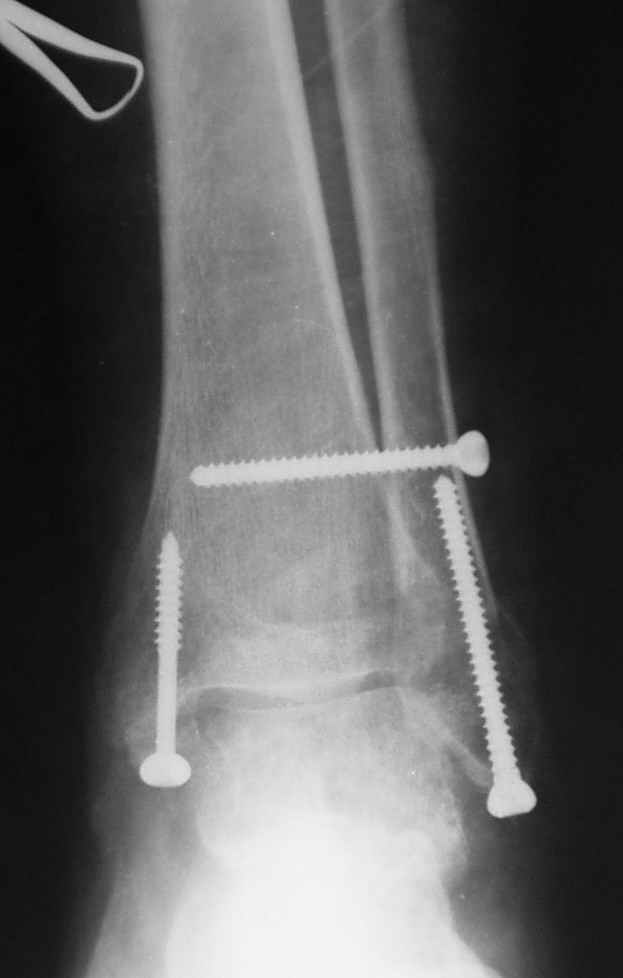

Боковой через месяц